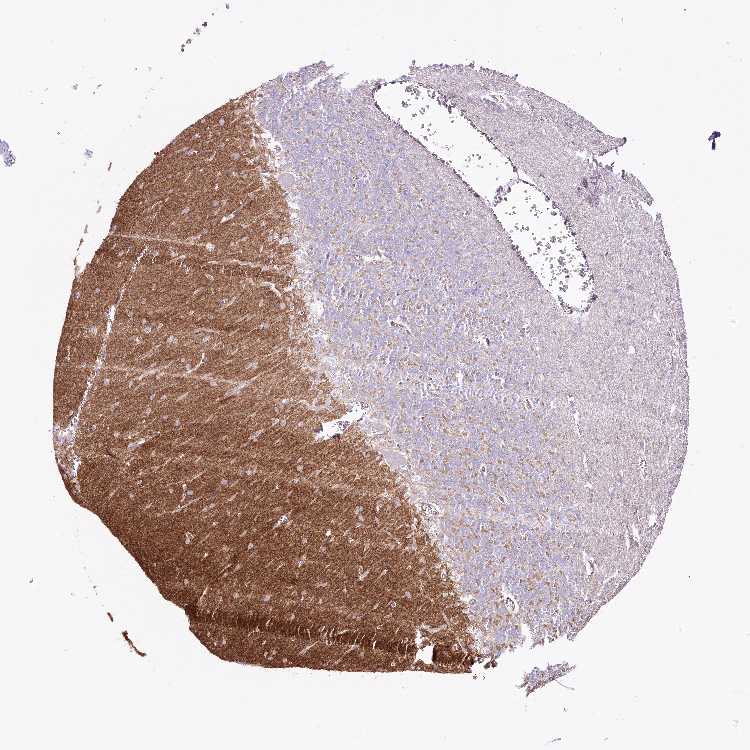

CEREBELLUM - Antibody stainingi

Antibody staining in the annotated cell types in the current human tissue is reported as not detected, low, medium, or high, based on conventional immunohistochemistry profiling in selected tissues. This score is based on the combination of the staining intensity and fraction of stained cells.

Each image is clickable and will lead to virtual microscopy that enables deeper exploration of all samples and also displays staining intensity scores, fraction scores and subcellular localization as well as patient and tissue information for each sample.

Antibody HPA038286

Purkinje cells Not detected

Cells in granular layer Not detected

Cells in molecular layer Not detected